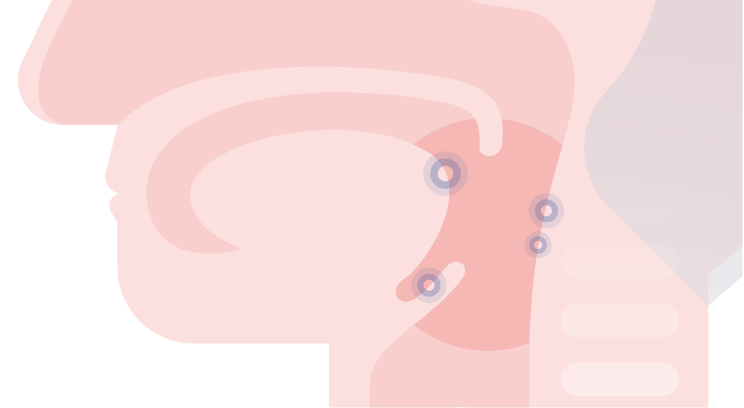

Desondanks is de prognose voor HPV-positieve tumoren in het algemeen beter, ongeacht de toegepaste therapie (chirurgie, chemo- en/of radiotherapie).